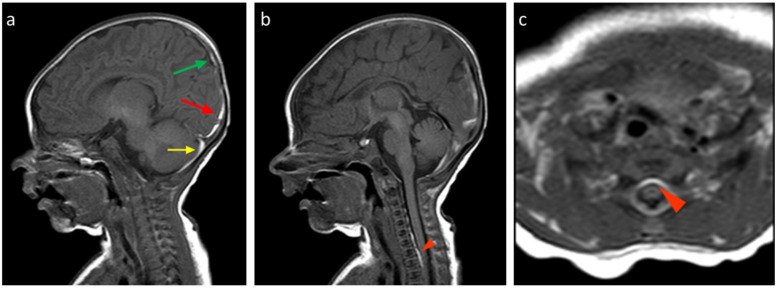

Background: Neonatal birth-related intracranial subdural hemorrhages (SDHs) represent a form of bleeding inside the skull that occurs in newborns. This condition includes the extravasation of blood both in the encephalic parenchyma and in the extra-axial spaces. Recent studies have shown that SDH and particularly post-traumatic birth-related hemorrhages represent a frequent occurrence, but they are often asymptomatic. The gold standard for the diagnosis and follow-up of patients with SDH is multiparametric Magnetic Resonance Imaging. The aim of this study is to describe our experience by reporting several cases of SDH with different distribution and Central Nervous System involvement by the MRI of this pathology in infants up to 30 days of age. Methods: We analyzed the age and sex of the patients included in this study, the localization of SDH in different CNS areas, and their frequency using distribution plots and pie charts. Results: About the analysis of the SDH locations in the 32 patients, the most common location was the cerebellum (31/32, 96.9%), followed by parietal and occipital lobes (19/32, 59.4%; 18/32, 56.2%, respectively), falx cerebri (11/32, 34.4%), tentorium cerebelli (10/32, 31.2%), temporal lobes (6/32, 18.7%), and finally cervical and dorsal spine in the same patients (4/32, 12.5%). According to SDH locations, the patients were divided into supratentorial, infratentorial, both, and Spinal Canal. Conclusions: Our study confirmed the literature data regarding the neonatal birth-related SDH high frequency, but also allowed us to focus our attention on the rarest spinal SDH localizations with the same benign evolution.

背景:新生儿出生相关的颅内硬膜下出血(SDHs)是新生儿颅骨内出血的一种形式。这种情况包括脑实质和轴外间隙的血液外渗。最近的研究表明,SDH,特别是创伤后出生相关出血是一种常见的情况,但它们通常是无症状的。多参数磁共振成像是SDH患者诊断和随访的金标准。本研究的目的是通过报告几个不同分布的SDH病例来描述我们的经验,并通过MRI对30天以下婴儿的这种病理进行中枢神经系统受累。方法:采用分布图和饼状图分析本组患者的年龄、性别、SDH在中枢神经系统不同区域的定位及发生频率。结果:32例患者SDH发生部位分析中,以小脑最多见(31/32,96.9%),其次为顶叶和枕叶(19/32,59.4%);分别为18/32,56.2%),大脑镰(11/32,34.4%),小脑幕(10/32,31.2%),颞叶(6/32,18.7%),最后是颈椎和脊柱背(4/32,12.5%)。根据SDH的位置,患者分为幕上、幕下、两者和椎管。结论:我们的研究证实了文献中关于新生儿出生相关SDH高频率的数据,但也使我们能够将注意力集中在具有相同良性进化的罕见脊柱SDH定位上。